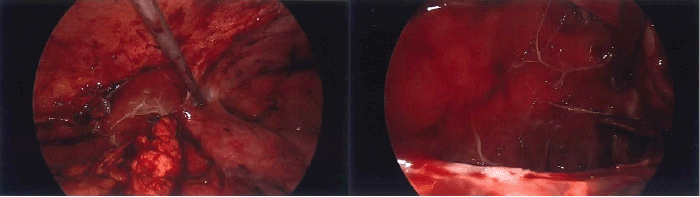

Figure 1. CT Findings of Abdominal Pseudocyst. Published with Permission

(A) Coronal view highlighting the extensive nature of the pseudocyst (red arrow). (B, C) Axial views showing the large APC containing the distal VP shunt catheter tip and demonstrating significant mass effect

Upon presentation to our institution, the patient was hemodynamically stable and afebrile. Physical examination revealed severe abdominal distension with mild tenderness localized to the lower abdomen, but without signs of peritonitis. No focal neurological deficits were observed. Labs were significant for leukocytosis at 17.9 × 109/L and hyponatremia (128 mmol/L). A repeat CT of the abdomen/pelvis revealed a large abdominopelvic cystic collection measuring 17.0 × 14.5 × 11.0 cm, consistent with a VP shunt-associated abdominal pseudocyst (APC). This collection exerted significant mass effect upon the right ureter, resulting in moderate right-sided hydronephrosis (Figure 1). Broad-spectrum intravenous antibiotics were initiated.